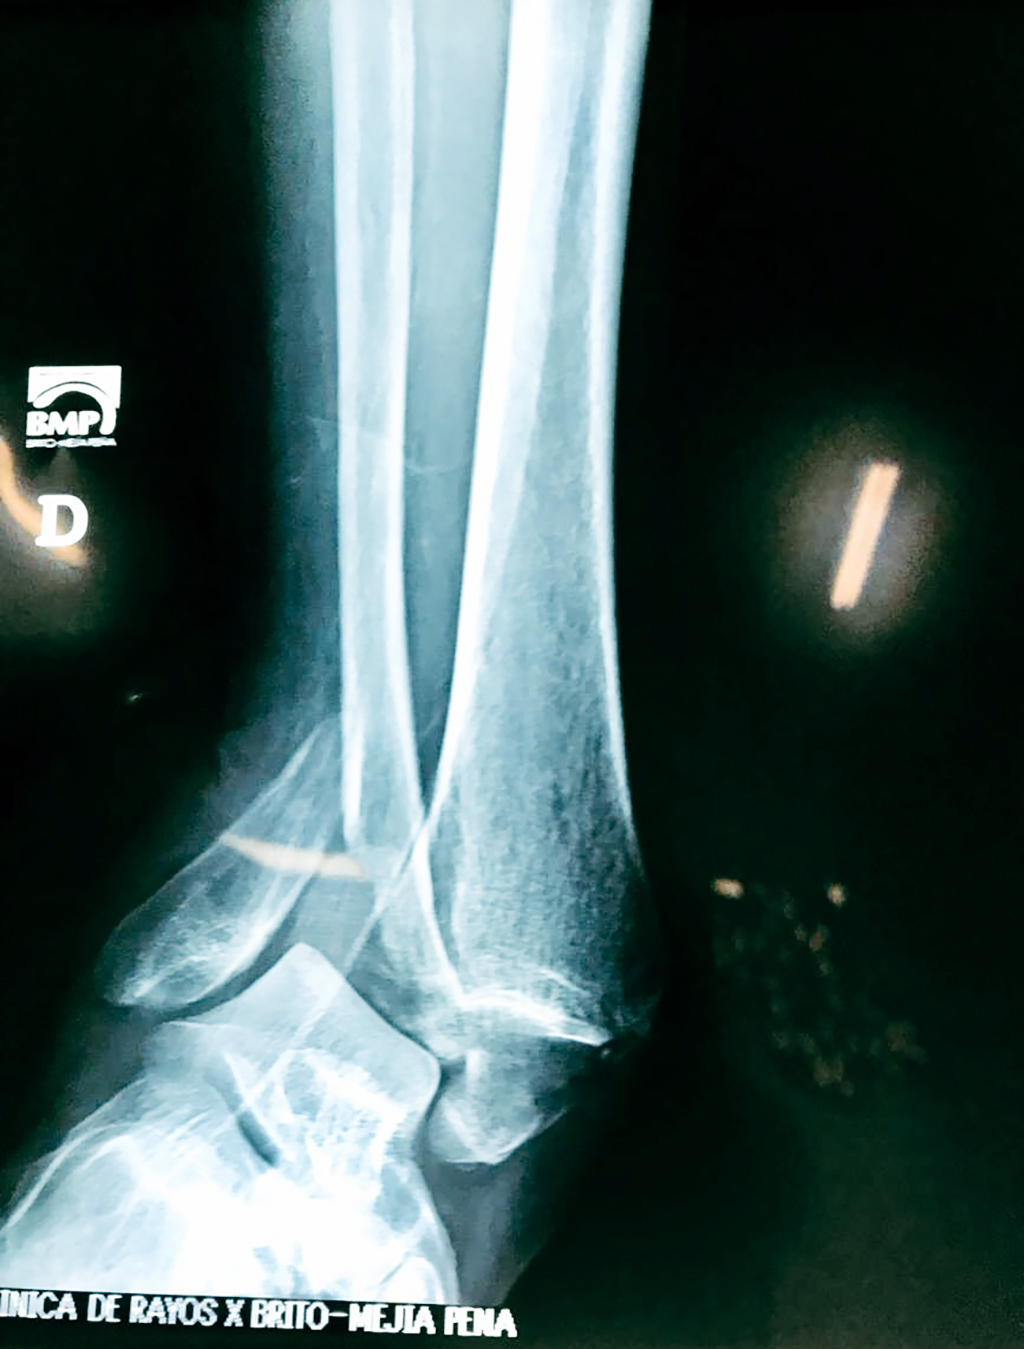

Una fractura de tobillo es la rotura de uno o más de los huesos del tobillo. Estas fracturas pueden ser:

- Parciales (el hueso está sólo parcialmente fisurado, no del todo).

- Completas (el hueso está perforado y está en 2 partes).

- Producirse en uno o ambos lados del tobillo.

Algunas fracturas de tobillo pueden requerir cirugía si:

- Los extremos de los huesos están desalineados entre sí (desplazados).

- La fractura se extiende hasta la articulación del tobillo (fractura intra-articular).

- Los tendones o ligamentos (tejidos que sujetan los músculos y los huesos entre sí) están rotos.

- El médico cree que sus huesos probablemente no sanen apropiadamente sin cirugía.

- El médico considera que la cirugía puede permitirle una recuperación más rápida y confiable.

- En los niños, la fractura involucra la parte del hueso del tobillo donde el hueso está creciendo.

Cuando se necesita cirugía, es probable que esta implique el uso de clavijas de metal, tornillos o placas para sostener los huesos en su lugar mientras la fractura se consolida. Los elementos de soporte pueden ser temporales o permanentes.